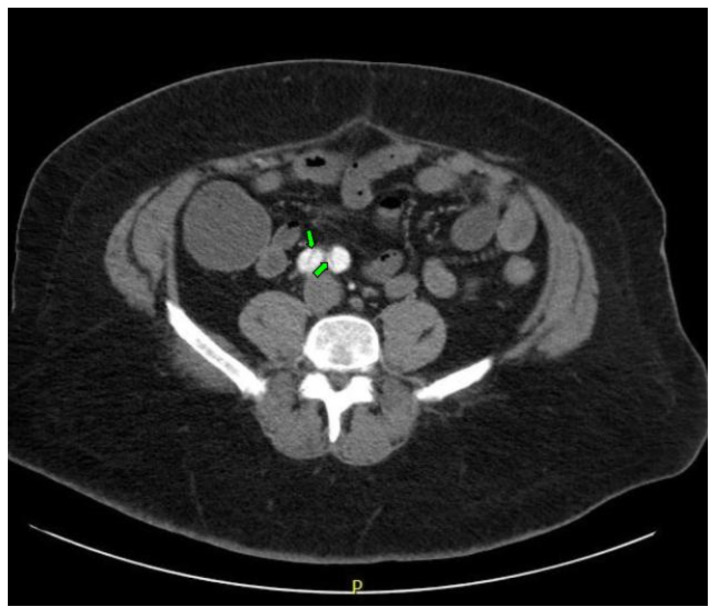

Computed tomography angiography (CTA) of the thoracic and abdominal aorta revealed an aortic dissection of the ascending aorta, with a dissection flap starting from the aortic root/aortic annulus (yellow arrows), extending into the aortic arch (light blue arrowhead) and involving the left common carotid artery (purple arrow), left subclavian artery (pink arrow), extending to the descending aorta (red arrows), and into the bilateral iliacs (green arrows). The true lumen (red star) and false lumen (blue star) created by the dissection flap can best be seen in the axial views. Laboratory findings revealed a mild leukocytosis with a white blood cell (WBC) count of 14.6 (reference range 4.0–10.5 WBC’s × 109 per L), but were overall insignificant with a lactate level of 1.3 mmol/L (0.5–2.0 mmol/L) and a high sensitivity troponin I of 13 ng/L (0–20 ng/L).